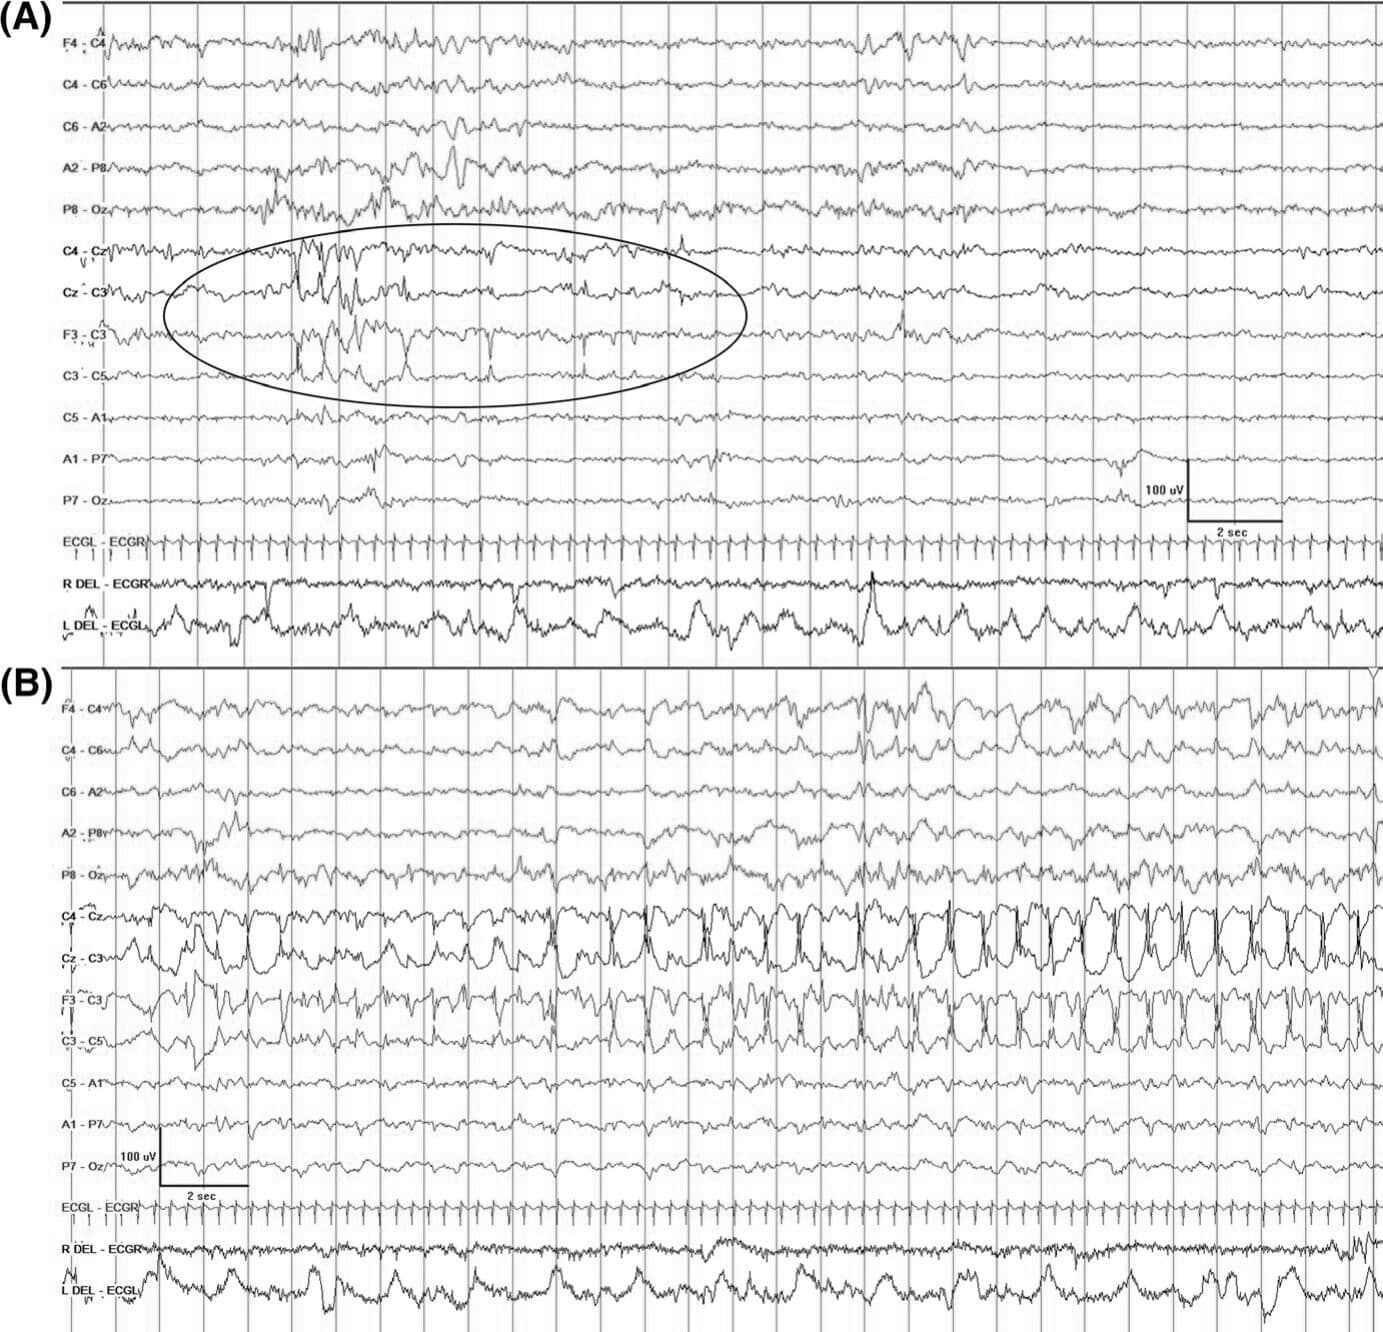

| 单纯电发作 | 亚临床,没有临床表现 | 必须有EEG/aEEG | 常见于早产儿、HIE(尤其是那些基底节或丘脑损伤的患儿)、病情危重者以及接受心脏外科手术的新生儿 | 9,11,15,81,106-109 |